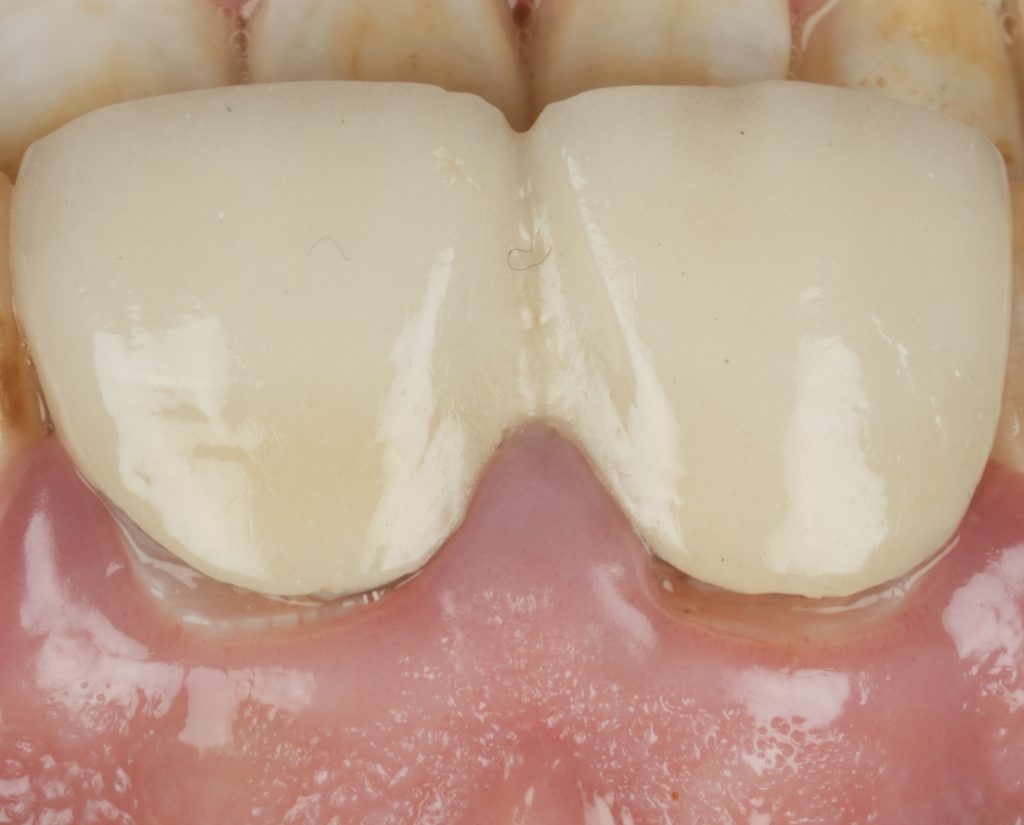

IPS E-max Press veneers were pressed and characterized using micro-layered incisal ceramics for vitality and translucency. Surface texture and internal effects were customized to simulate natural perikymata and halo zones (Fig 3).